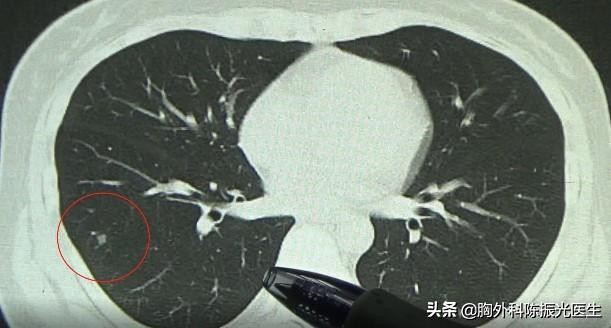

从蒋女士发过来的报告和片子上可以看到,她主要的问题是在右下肺的前段。这个结节是个半实性的结节,既有磨砂玻璃的成分,也有实性的成分。另外要注意的是,从片子上隐隐约约能看见一个血管束进入这个结节里面。

所以像这样的结节,我建议2种处理方法:

(1)密切观察,每三个月观察一次 ,同时也要观察肺肿瘤标志物的改变;

(2)如果这个朋友愿意,可以局部在微创下面做切除、活检,明确到底是不是癌变的结节。